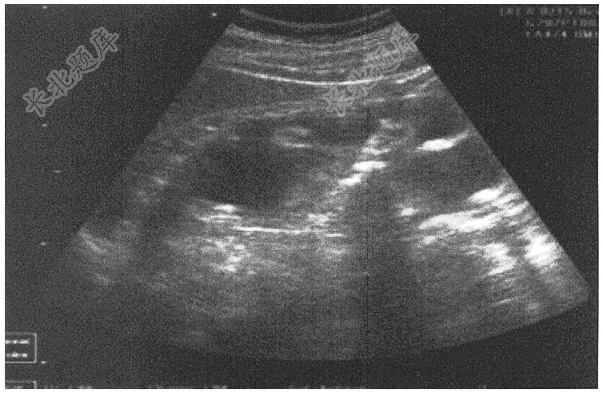

- 简答题患者,男,32岁,体检B超如下图,请进行简单描述和写出主要诊断